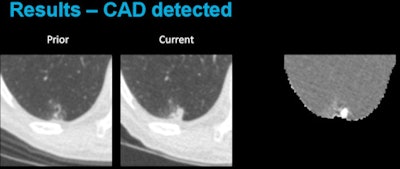

Above, CAD applied to subtraction-based registration of prior and current lung CT images detected a new nodule. Below, CAD did not detect a new nodule at the lung base that was not present on the baseline scan. All images courtesy of Colin Jacobs, PhD.The purpose of the study was to compare the automated detection of interval changes at low-dose lung cancer screening CT with manual reading between low-dose CT images in a lung cancer screening setting using analysis of subtraction images.

Given a current and prior scan, the registration method outputs a deformation field and uses it to generate a deformed prior scan, Jacobs explained. The deformed prior scan can then be subtracted from the current scan to create a subtraction image.

In the CAD process, images are analyzed and potential areas of interval change are extracted using banded thresholding and connected component analysis. Then, for each candidate, a set of intensity, shape, and context features is calculated and a GentleBoost classifier is used to distinguish between relevant changes and registration artifacts.